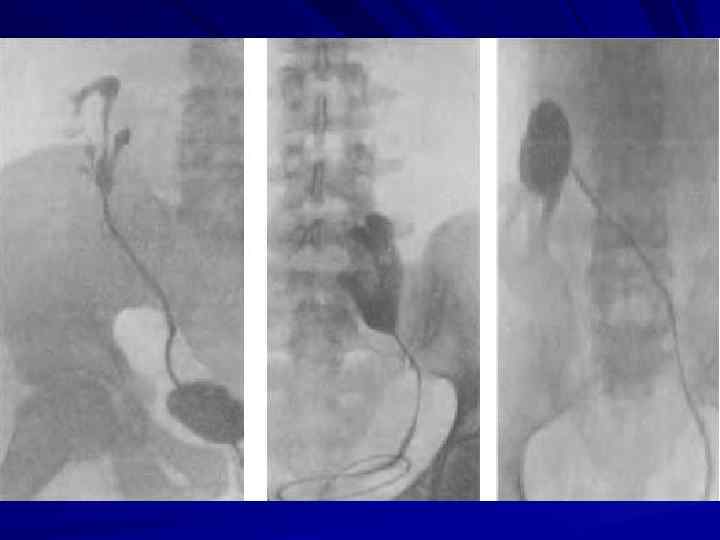

АНОМАЛИИ РАЗВИТИЯ МОЧЕПОЛОВОЙ СИСТЕМЫ

Сосудистая ножка почки